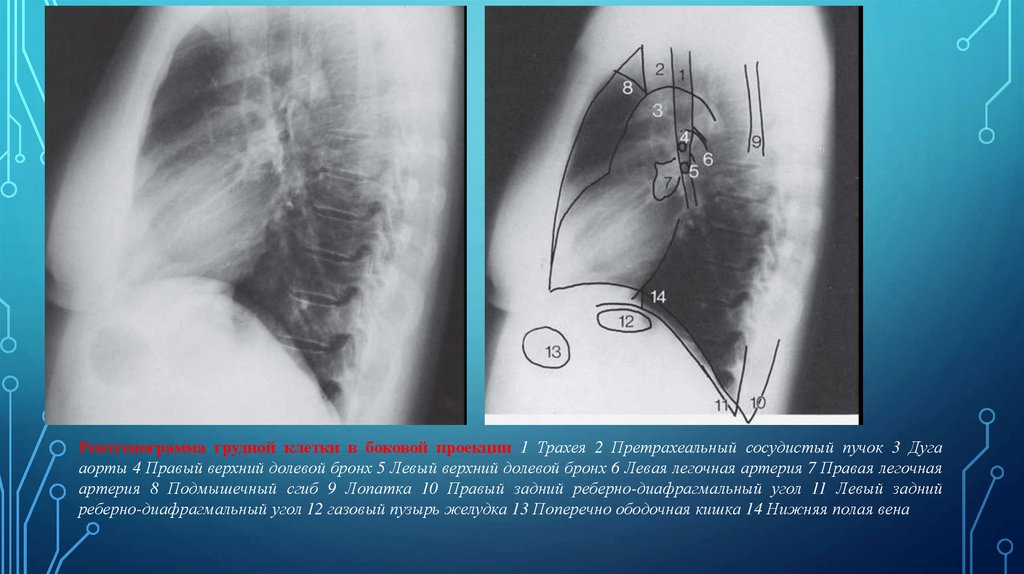

Рентгенограмма грудной клетки в боковой проекции 1 Трахея 2 Претрахеальный сосудистый пучок 3 Дуга

аорты 4 Правый верхний долевой бронх 5 Левый верхний долевой бронх 6 Левая легочная артерия 7 Правая легочная

артерия 8 Подмышечный сгиб 9 Лопатка 10 Правый задний реберно-диафрагмальный угол 11 Левый задний

реберно-диафрагмальный угол 12 газовый пузырь желудка 13 Поперечно ободочная кишка 14 Нижняя полая вена